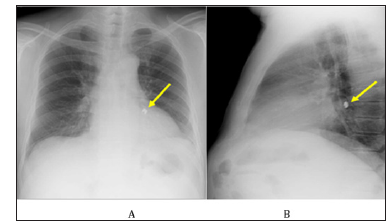

A 57-year-old male diagnosed with schizophrenia had been treated for tooth decay. During covering a dental crown, the palladium was dropped in the oral space. He had a continuous cough and was suspected of aspiration of the dental crown thus he was transferred to another hospital. Chest radiography showed a metallic foreign body in the left lower lung field (Figures 1A & 1B) and he visited the emergency department of our hospital. Chest computed-tomography showed an artifact, that is, a foreign metal body in the left basal segmental bronchus of B9 of the lung (Figures 2A-2C). An endobronchial foreign body was diagnosed, and endoscopic removal was scheduled as the first steps before surgical removal. Under airway anesthesia, a flexible bronchoscopy was guided to the stuck dental crown in the B9 endobronchus (Figure 3A), which was grasped (Figure 3B) and successfully removed by alligator forceps. As the dental crown is made of palladium with a smooth surface, and firmly fixed the peripheral bronchus, it should be difficult to remove, however, we could strongly grasp it using alligator forceps for a digestive endoscope.

Figure 1: Chest radiographic film.

A. A small metal (the dropped dental crown) was located in the left lower airway (yellow arrow).

B. The foreign body was located in posterior and lower airway (yellow arrow).

Foreign body aspiration is an uncommon clinical entity in adults [8,9]. A foreign body in the bronchial airway is commonly known to be found in infants and in elderly people, in contrast, few occur in middle age adults and seniors without basic diseases. Identification of a foreign body aspiration requires a high index of clinical suspicion, especially in those presenting without a history of aspiration. The radiological manifestations of foreign bodies or indirect signs (representing airway obstruction) occur in the form of nonresolving pneumonia, athelectasis, unilateral hyperinflation, or localized bronchiectasis, especially in those with organic foreign bodies [1,10,11]. This is explained by the anatomical features of the right main bronchus, which is wider in diameter, shorter in length, and has a more direct extension of the trachea than the left bronchus [7]. The most common location for a foreign body in the airway is the right bronchial tree, particularly, the right lowerlobe of the right main bronchus [8]. Further more, the left main bronchus does not branch at the same acute angle [7]. Two-thirds of aspirated objects lodge in the main bronchi rather than in the distal bronchi [3]. In this case, the foreign body was dropped in the left distal bronchi (Figures 1A & 1B). Bilateral foreign bodies were present in only one subject and are rare. The foreign bodies could not be identified in 25% of the subjects possibly due to spontaneous expulsion of the foreign body, dissolution of an organic foreign body, or embedding of a small foreign body in the granulation tissue or edematous mucosa [1].